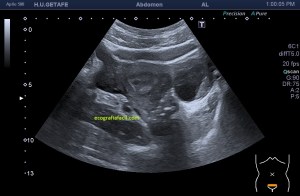

Durante la exploración de una eco de abdomen en el contexto de un paciente que acude por elevación de transaminasas observo una imagen heterogénea, irregular, con una pared marcadamente calcificada, bilobulada de gran tamaño que medí en dos partes ya que me pareció claramente que estaban diferenciadas.

Una de ellas, la primera, era mucho más hiperecogénica y más pequeña, su centro estaba mas calcificado, su sombra acústica posterior era mucho más acuciada y llamaba más la atención. Justo al lado, otra lesión de mayor tamaño, su calcificación era mucho más sutil y más periférica delimitando una LOE hipoecogénica de un tamaño muy importante, adyacente a la más pequeña, como he comentado previamente. Ambas sin señal Doppler.